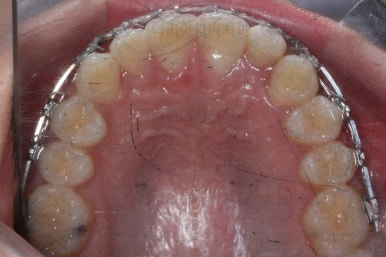

마찬가지로 부산교정치과 키다리아저씨치과에 처음 내원하셨을 당시의 입안 모습입니다.

화살표로 표시된 치아가 작은 앞니 부분인데 크기가 매우 작고 뾰족한 것을 볼 수 있어요. 유치가 아니고 평생 써야 하는 영구치입니다. 이러한 상태를 "왜소치"라고 표현하는데, 치아 크기의 문제로 여러 가지 문제점이 생길 수 있어요.

윗니 치아 사이에 틈이 생길 수 있습니다.(치아 크기가 모자란 만큼 틈이 있는 것이죠.)

아래 앞니가 삐뚤어질 수 있습니다.(비율상 아랫니가 상대적으로 커지기 때문에 삐뚤어지게 됩니다.)

미적으로 좋지 못합니다.

또 다른 문제는 위아래 앞니가 매우 많이 겹쳐져 있어서 아래 앞니가 거의 보이지 않는다는 점입니다.

작은 앞니가 왜소치이다 보니 윗니에는 틈이 남아있고 교합도 조금 엉성한 모습이에요.